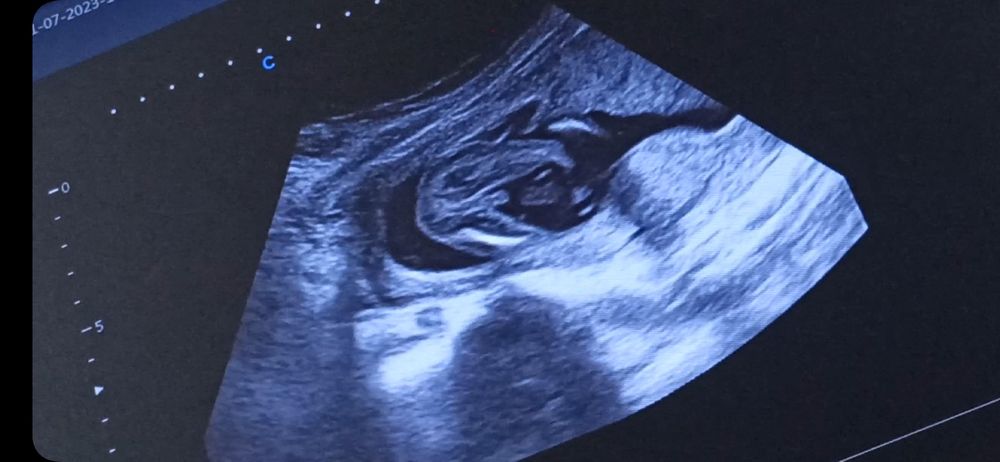

УЗИ в 17 неделек. Пол?

Пол малышаВопрос знатокам? Кто разбирается? Это мальчик или девочка?

Прикрепляю несколько противоречивых скринов с видео.

Врач очень не уверена предположила. Малыш крутился.

Как будто фотки разных детей) первая как девочка, а дальше уже больше на мальчика.

Антонина Соколова, по первым фото похожа на девочку .Но дальше есть что -то … пусть будет пуповина. Первое фото это скрин с видео ,я там прокручиваю и смотрела ,попробуйте и вы ,чтобы понять что там между ножек

Татьянка, я так и делала. Это всё скрины с одного минутного видео. Уже поставила на замедленное воспроизведение, смотрела изучала. Весь инет перерыла сравнивала. Ну чисто 50/50)))) кума говорит, на девочку похожа, я думаю что похоже на мальчика, муж бредит девочкой и говорит мне, что у мальчиков мошонка должна быть и где она, её нет. Врач предположила мальчика. Но не уверенно.